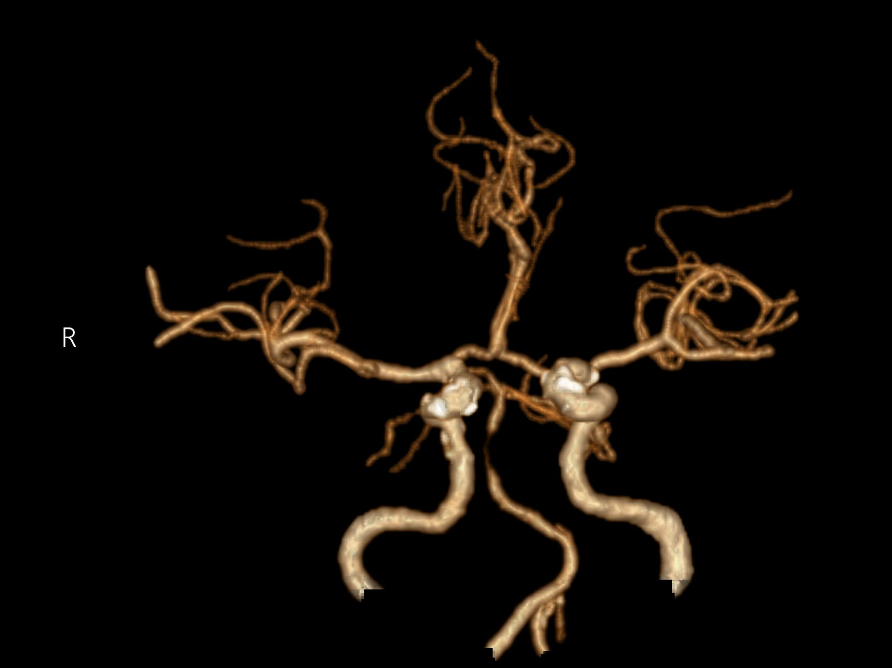

今年12月,王爷爷又因反复头晕回来复查。血管造影提示,基底动脉中段出现了重度狭窄(如图1),血管斑块处于不稳定状态(如图2),就像一颗“定时炸弹”,随时可能再次引发卒中,具备强烈的手术指征。

图1:头颈部CTA:基底动脉重度狭窄。